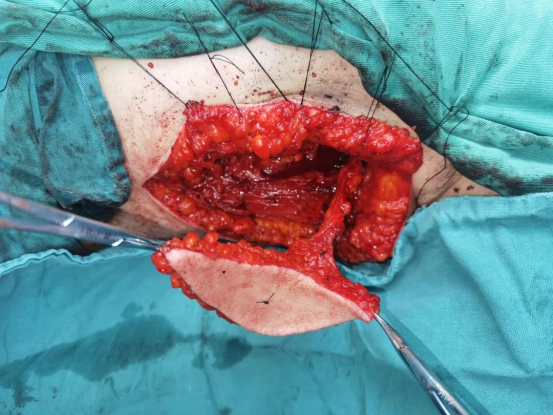

术中图

在麻醉医师和手术室医护人员的共同努力下,刘睿医师团队历经8小时,按计划顺利完成手术。经过口腔颌面外科全体医护人员的精心治疗和护理,患者口内皮瓣愈合良好,舌体活动度良好,语音及进食功能无明显影响,口内外伤口均恢复良好,患者顺利出院,并对治疗效果表示非常满意。